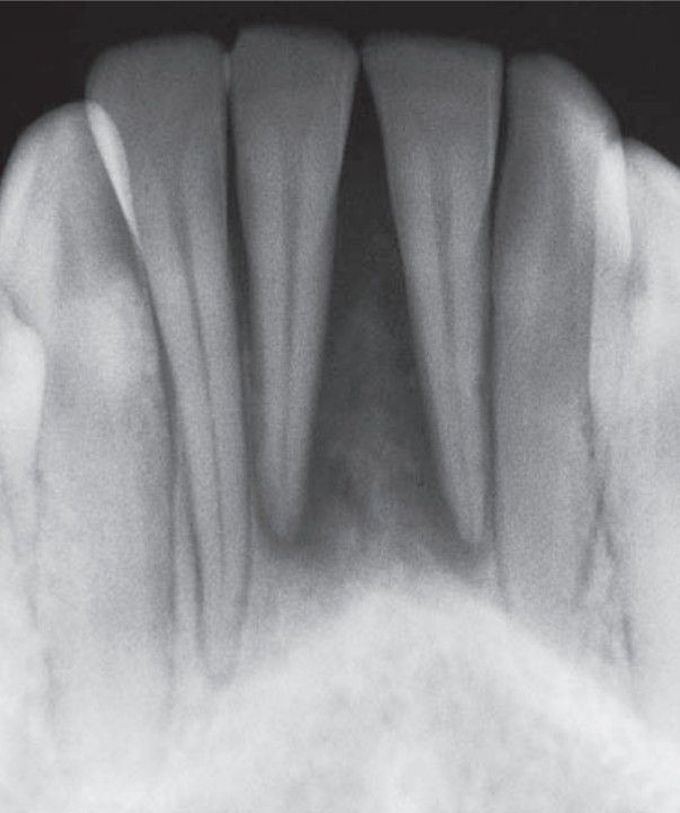

Metastatic osteosarcoma to anterior mandible

Pain or paresthesia common; origin is most likely from a malignancy of breast, kidney, lung, colon, prostate, or thyroid.